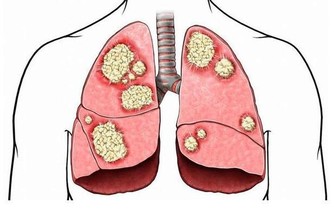

吸煙時會吸入幾十種致癌物質和上千種有害物質,這些有害物質會不斷侵入身體的各個部位,給身體健康帶來危害,尤其是我們的大腦,加速大腦的衰退機率